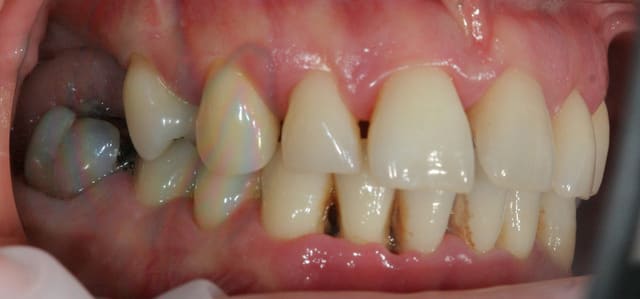

Paro ultra agressive chez une jeune femme de 30 ans.

Dans toute cette période, je n'ai pour ainsi dire quasiment jamais eu de cas de parodontite agressive aussi importante que celle ci.

Je me pose des questions non pas sur le traitement mais sur vos avis quant à la prédictibilité du traitement.

la patiente est très jolie, elle a 30 ans, a consulté deux ou trois dentiste en l'espace de 10 ans, le dernier détartrage date il y a trois ans et il n'a pas été terminée apparemment car la patiente avait trop de douleurs, et aujourd'hui elle est adressée par un hôpital parisien qui devait lui poser des implants et qui devant la panoramique a renoncé sans pour autant la diriger correctement.

Une contention sera réalisée en bas (mobilités très importantes) . En haut curieusement il n'y a que très peu de mobilités.

PS : ce qui me donne pas mal d'espoir dans ce cas-là, c'est tout de même les nombreuses lésions angulaires, qui vont bien accepter la pose de biomatériaux.